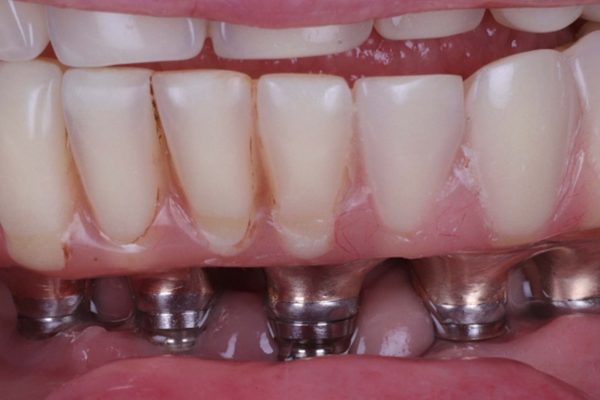

Figures 1-3 show a 90-year-old patient, who presented with a fractured 26-year-old implant bridge. This bridge has been in place for 24 years without incident. The patient was very happy with it.

From my discussion with the patient, along with my assessment and radiograph (shown in Figure 4) I was able to find out this patient had been treated with Branemark implants, and the restoration was an acrylic bridge with a gold framework.

When the implant bridge was off, I was able to irrigate the area and remove the soft plaque deposits present (Figures 5 and 6).

The occlusion and aesthetics were checked, and the patient was delighted that we’d managed to refurbish the bridge and achieved her goals. The final result is shown in Figures 7-11.